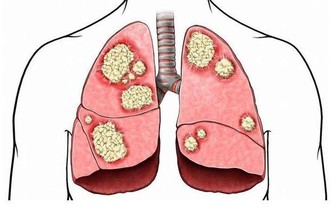

因為人體循環是從上往下,當人體內毒素較多的時候,毒素首先堆積的地方就是肩頸,

因為肩頸是人體的十字路口,毒素堆積就會造成肩頸硬化、衰老。